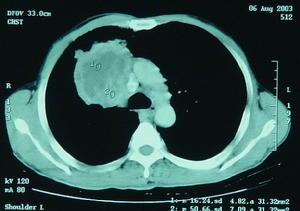

CT 檢查可進一步發現壞死性肺炎時出現的多發的小膿腔。